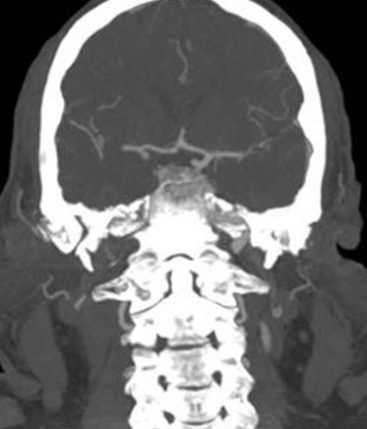

1. Occlusion of the right internal carotid artery (R-ICA intracranial segment) involving P-Com & AChA.

2. Occlusion of the right P-Com in the context of a fetal type PCA.

3. A patent apex of the right carotid artery with normal intracranial circulation elsewhere.

24-hr CT showed a small lesion in the anterior portion of the right thalamus and a marginal lesion in the adjacent right internal capsule